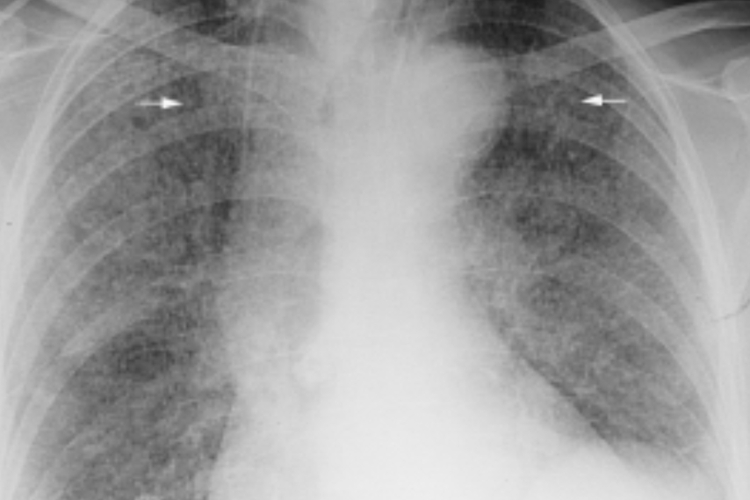

急性血行播散型肺结核:表现为由肺尖至肺底呈大小、密度和分布不均匀的粟粒状结节阴影,结节直径2mm左右。